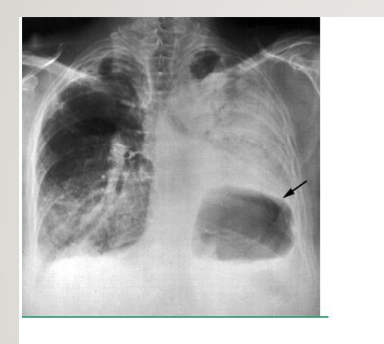

What is shown on the images?

pancoast tumour